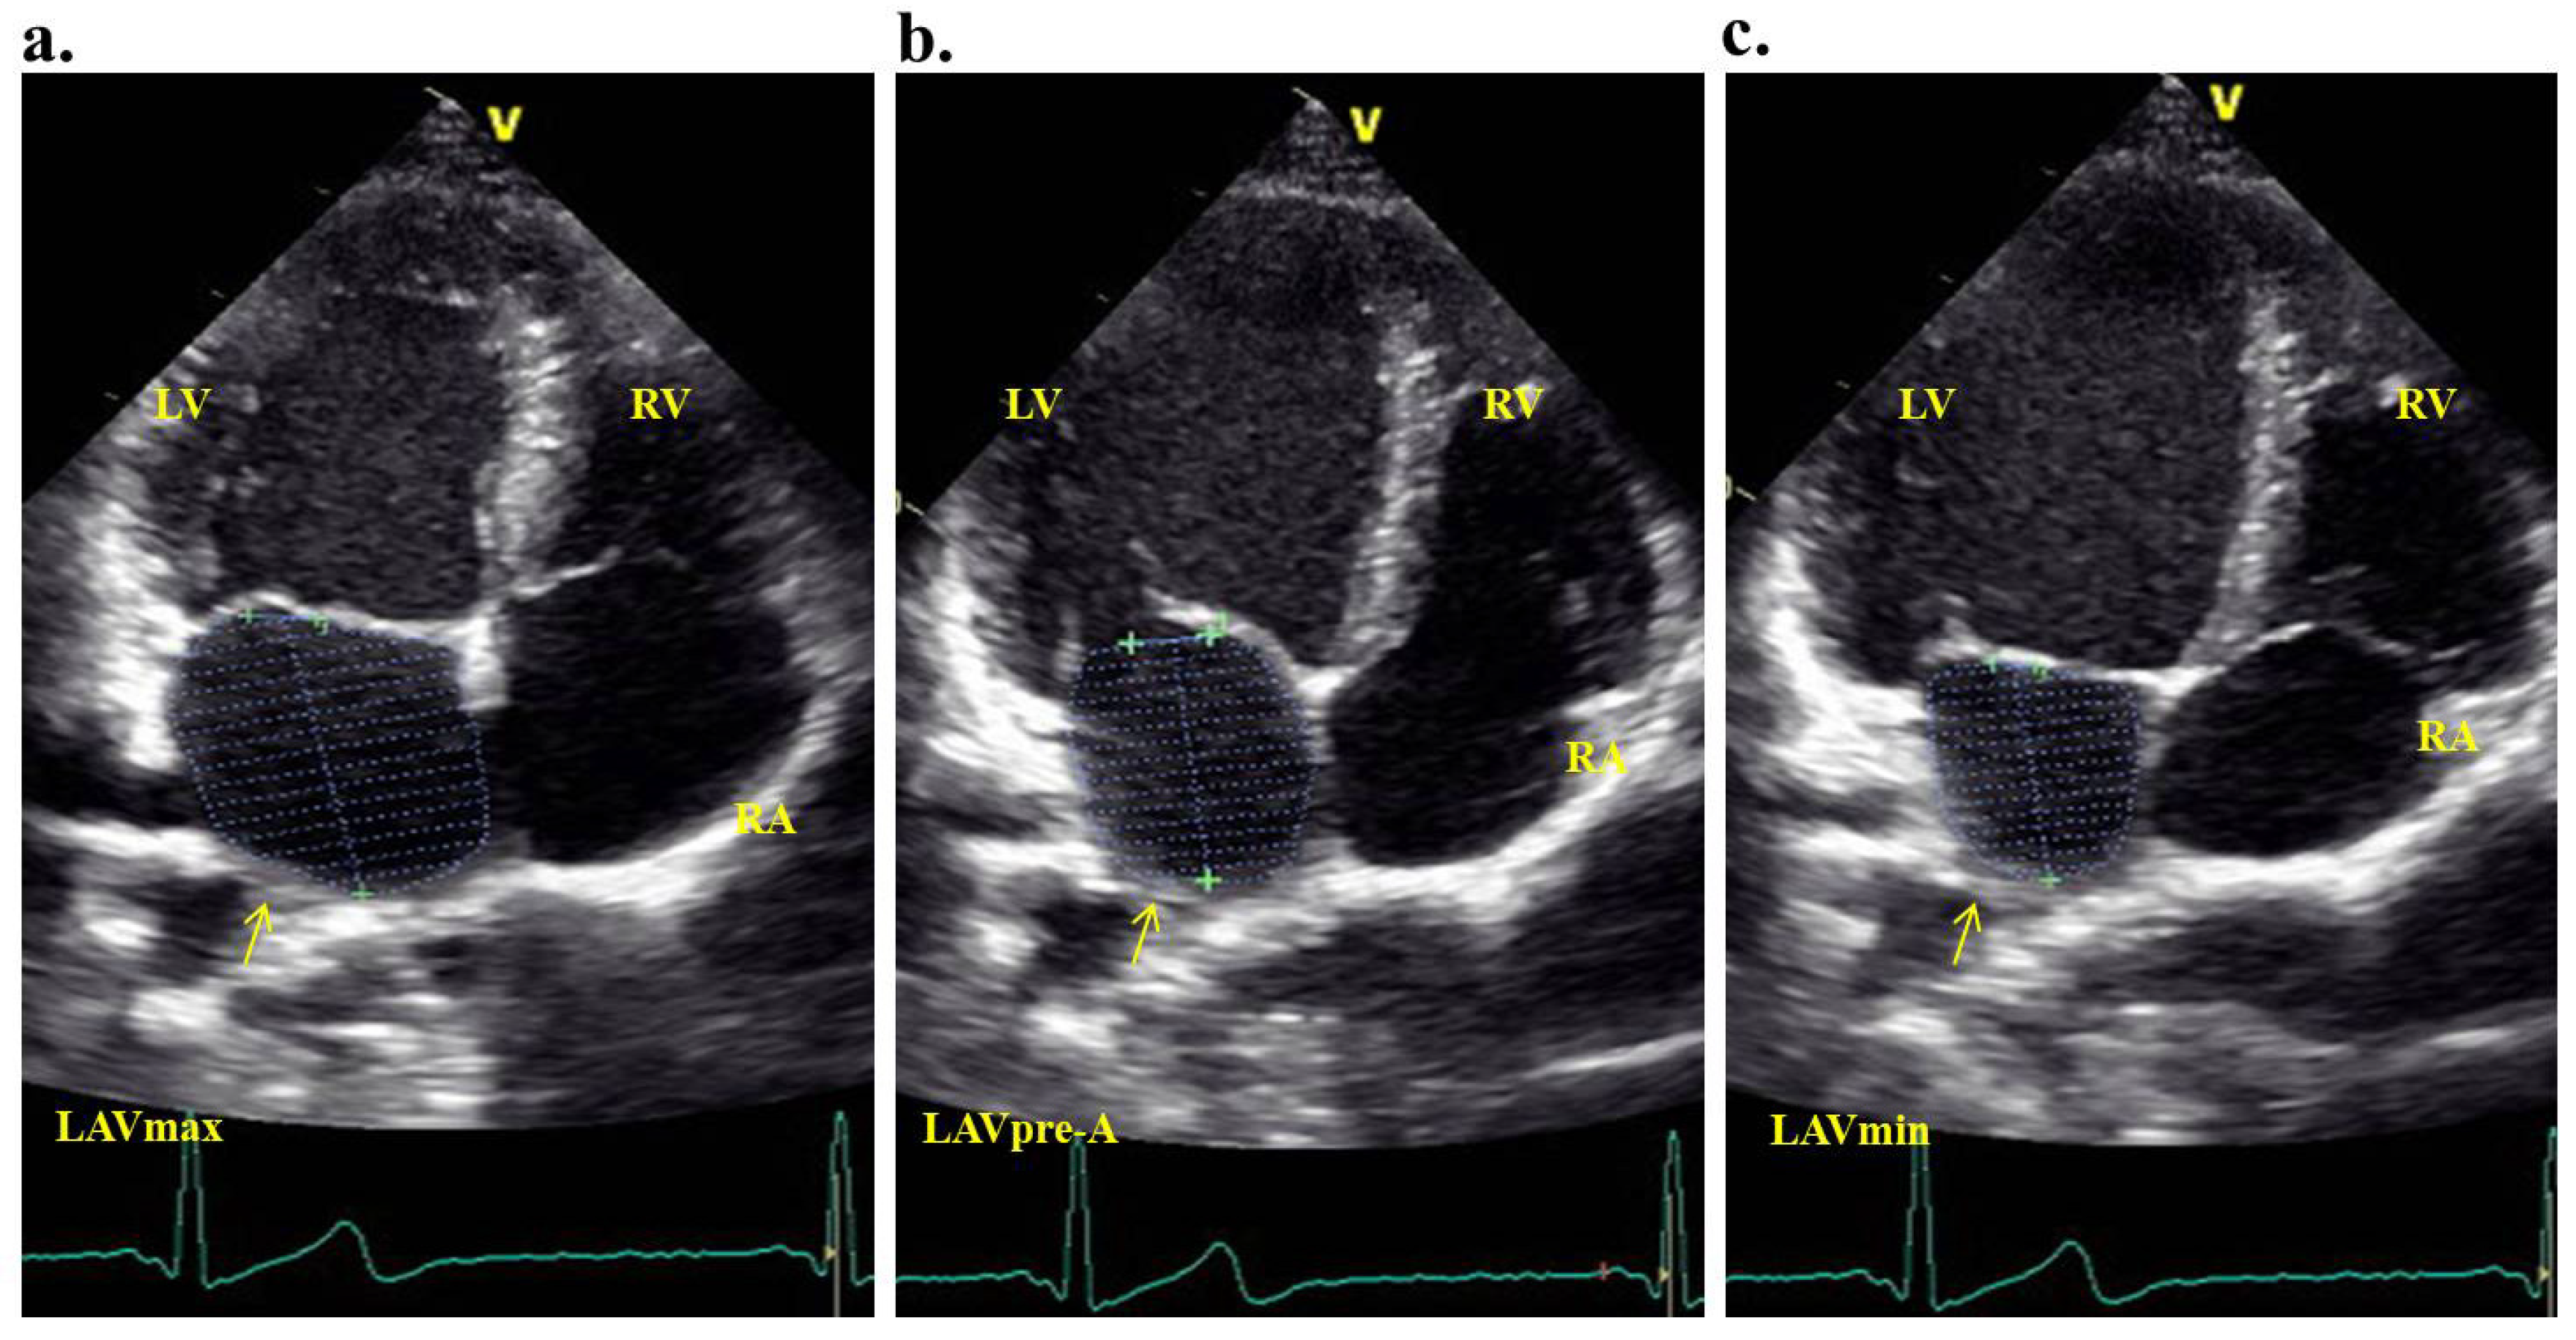

2.4. Evaluation of Left Atrial Mechanical Functions

Simultaneously with the echocardiography, an electrocardiogram was recorded. Measurements were documented over three consecutive cardiac cycles. All atrial volumes were derived from the apical four-chamber perspective. When outlining the boundaries, we encompassed the left atrial walls, excluding the pulmonary veins and the left atrial appendage. The left atrial volume index (LAVI) was determined by dividing the left atrial volume by the body surface area of the patient. We computed the maximum left atrial volume (LAVmax), the minimum left atrial volume (LAVmin), and the precontraction left atrial volume (LAVpreA) (Figure 2a–c).

Figure 2.

Maximum (a) atrial precontraction (b) and the minimum (c) volume measurements of the left atrium were made by transthoracic echocardiography on an apical four-chamber window (LV = left ventricule; RV = right ventricule; RA = right atrium; LAVmax = left atrium maximal volume; LAVpre-A = left atrial precontraction volume; LAVmin = left atrium minimum volume).